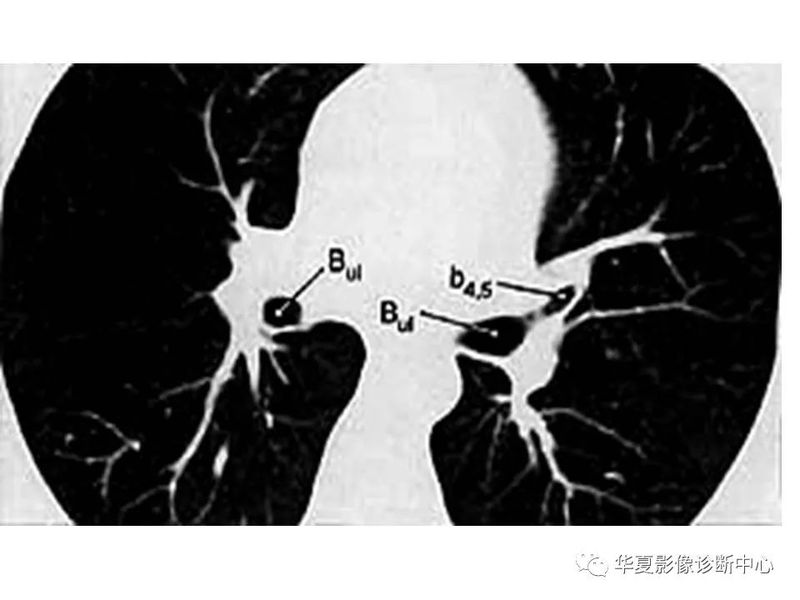

干货 | 汇总胸部CT读片扫盲知识,看懂胸部CT不再难